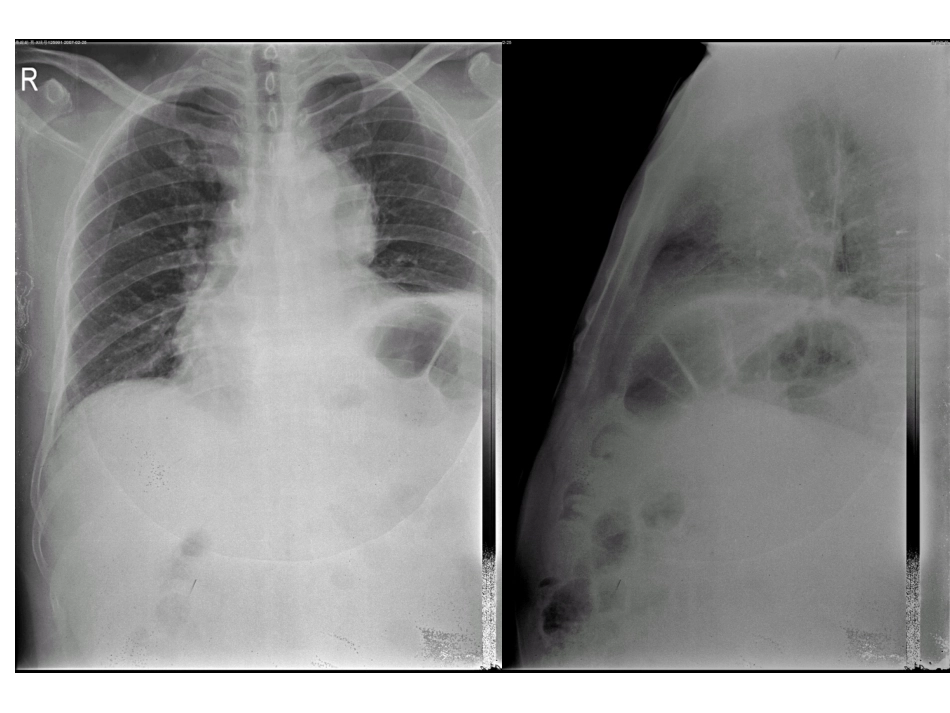

病例讨论唐都医院放射科朱佳病史资料•患者,男,53岁•现病史:于10天前感左肩疼痛,为持续性钝痛,于交大一附院CT检查:前上纵隔占位性病变。•查体未见异常。•术中所见:左前上纵隔包块,大小约为8X8X5cm,质硬,活动度小,基底较宽,无包膜,与左肺下叶、侧胸壁、心包、主动脉弓有粘连,胸腔有淡红色积液,约200ml,膈肌明显升高,右肺下叶内基底段实变,鼓肺后基本复张。•病理:(纵隔)大细胞型(不典型性)尤文氏肉瘤。概述•骨外尤文氏肉瘤是一种少见的软组织恶性小细胞性肿瘤[1]。可发生于任何年龄,但多见于青年人,比骨内尤文氏肉瘤的发病年龄大。肿瘤多发生于躯干,尤以下肢、脊柱旁、腹膜后和胸壁多见,约1/3见于四肢,这与骨内尤文氏肉瘤多见于下肢骨(尤以胫骨)不同。•1.武中弼,杨光华.中华外科病理学[M].北京:人民卫生出版社。2OO2.2741—2742.发病情况•骨外尤文氏肉瘤好发于10~30岁青少年,平均约20岁,多见于男性,多发于脊柱旁、腹膜后和胸部软组织及下肢,好发部位较深,生长较快。本病例发生于纵隔,尚未见文献报道。而骨尤文氏肉瘤发病年龄高峰为10~15岁,比骨外尤文氏肉瘤高发年龄约小10岁,多见于长骨骨盆和肋骨[2]。•2.丈平,王瑾.骨外尤文氏肉瘤15例临床及病理分析[J].2006,9(27):946~947分类•骨外尤文氏肉瘤属软组织恶性小圆细胞性肿瘤,分为神经性与非神经性。神经性骨外尤文氏肉瘤与骨尤文氏肉瘤、原始性神经外胚层瘤无论在病理学上、基因表型上、染色体易位上均有共同之处,目前认为它们均来源于神经外胚叶,均属外周原始神经外胚层瘤家族[2]。•2.丈平,王瑾.骨外尤文氏肉瘤15例临床及病理分析[J].2006,9(27):946~947病理•骨外Ewing’S肉瘤多呈不规则分叶状或多结节状,质软而脆,切面灰黄色或灰褐色,常见大片坏死,出血和囊性变。光镜下见瘤细胞较均匀一致,呈圆形,细胞核圆形或卵圆形,核膜清楚,染色质细而分散,可见小核仁,胞浆少,界限不清,淡嗜伊红,可见不规则小空泡[3],核分裂相可见,但不多。瘤细胞排列成片或不清楚的小叶状,小叶之间为血管纤维组织间隔。肿瘤内有时可出现菊形团样结构,是肿瘤细胞围绕血管排列所形成,或是小的巢状细胞内糖原,位于一端所形成。•3.MPetkovie,GZamolo,DMuhvic,et.ThefirstreportofextraosseousEwing’ssa/~omaintherectovaginalseptum[J].Tumofi,2002,88(4):345—346临床表现•骨外尤文氏肉瘤常表现为生长迅速的深部软组织肿块,因位置深,故常延误诊断。肿瘤可累及骨膜,但不出现骨内Ewing肉瘤所特有的洋葱皮样放射学征象[4]。可累及神经或脊髓,产生进行性感觉或运动障碍,约1/3患者有疼痛症状。丈平等人报道11例均以发现软组织肿块就诊,影像检查均未见到邻近骨质破坏及洋葱皮样放射学征象。•4.安玉梅,王文杰.骨髓外尤文氏肉瘤1例报告[J].中华临床新医学,2003,3(9):77I影像学表现•在影像学方面骨外尤文氏肉瘤与传统的尤文氏肉瘤(骨尤文氏肉瘤)检查手段的选择有较大的不同。骨外尤文氏肉瘤因为少有直接侵犯骨质,且无明显钙化,X线征象表现为缺少钙化的骨外软组织阴影,而且没有骨尤文氏肉瘤所特有那种洋葱皮样放射学特征,由此可见x线摄片临床意义不大,只能作为有无肺转移的常规胸片检查。•CT多因出血坏死而显示密度不均,偶尔在肿块中心出现密度减低区域;CT增强无特殊变化。MRI主要显示是占位病变,T1为等信号多见,T1显示肿物信号略比肌肉信号低,T2高信号,强化效应明显,呈现不均匀改变。影像学表现•超声检查为低回声区或无回声区;血管造影不能明显地与正常组织区分。核素骨扫描对诊断骨外尤文氏肉瘤没有帮助.可检查肿瘤有无转移至骨骼[5]。•5.黄智邦,梁伟雄.骨外尤文氏肉瘤诊疗进展[J].岭南现代临床外科2007.7(6):464~465鉴别诊断•畸胎瘤典型的畸胎瘤表现为厚壁囊肿,密度不均,可见液性、脂肪密度、软组织密度和骨化、蛋壳样钙化影,容易鉴别。•淋巴瘤纵隔淋巴瘤常融合呈软组织肿块,密度均匀或不均匀,增强后CT值多增加30HU以上;除前纵隔肿块外,绝大多数患者在颈部和纵隔其它部位常有肿大的淋巴结;肺部浸润常见,胸膜心包侵及少见。治...